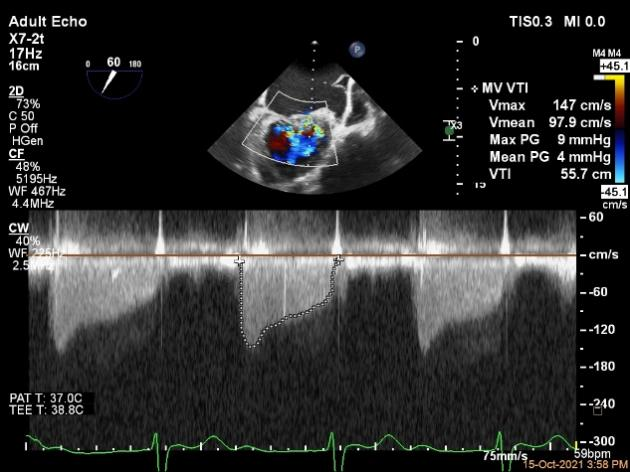

第一个夹子放置后二尖瓣口平均跨瓣压差:4mmHg

第二个夹子放置后二尖瓣口平均跨瓣压差:4mmHg

肺静脉血流频谱恢复正向